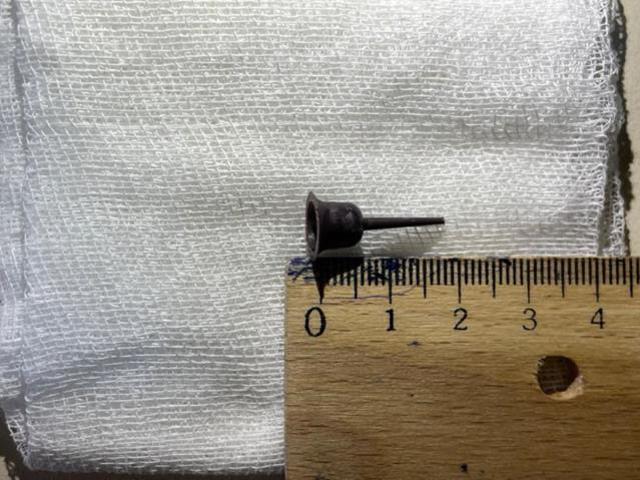

Göğüs Cerrahı Doç. Dr. Banu Yoldaş, Kalaycı'nın yaklaşık 9 yıldır soluk borusunda bulunan 2 santimetre büyüklüğündeki mum tutacağını ameliyatla çıkardı. Yoldaş, hastanın 15 gün önce kendisine başvurduğunda yaptığı kontrollerde yabancı cismin hava yolunu tamamen tıkadığını belirlediğini söyledi.

"2 SANTİMETRE BOYUTUNDA"

Hastasını acil olarak ameliyata alma kararı verdiğini belirten Yoldaş, şunları kaydetti: "Hastamızın akciğeri, geçirdiği enfeksiyonlara bağlı göğüs duvarına yapışmıştı. Ameliyatta önce bu yapışıklıkları gidermek zorunda kaldık. Tıkanmış olan hava yolunda ciddi enfeksiyon oluşmuş, sağ akciğerinin orta ve alt parçasının artık işlev görmemesine sebep olmuştu. Pasta mumlarında kullanılan 2 santimetrelik plastik tutacağı 4 saatlik bir ameliyatla hastamızın soluk borusundan çıkardık. Hastamız rahat nefes almaya başladı. Kısa süre sonra taburcu olmasını planlıyoruz." Ağız yoluyla yutulan cisimlerin soluk borusu ve akciğerde olumsuz sonuçlara neden olabileceğini dile getiren Yoldaş, nefes darlığı yaşayan kişilere mutlaka bir doktora başvurmasını önerdi.